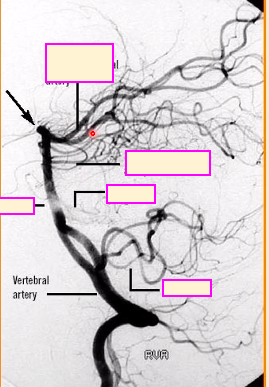

label A-D [4]

A: vertebral artery

B: superior cerebellar artery

C: posterior cerebral artery

D: basilar artery